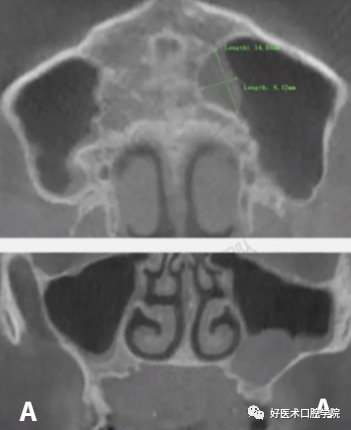

A:上颌窦粘液囊肿(周围可见骨质破坏) B:上颌窦积液(周围无骨质破坏)

1)术前CBCT测量:术前测量上颌窦底壁到牙槽嵴顶距离、上颌窦底壁到囊肿边缘的距离以及测量设计骨开窗位置。